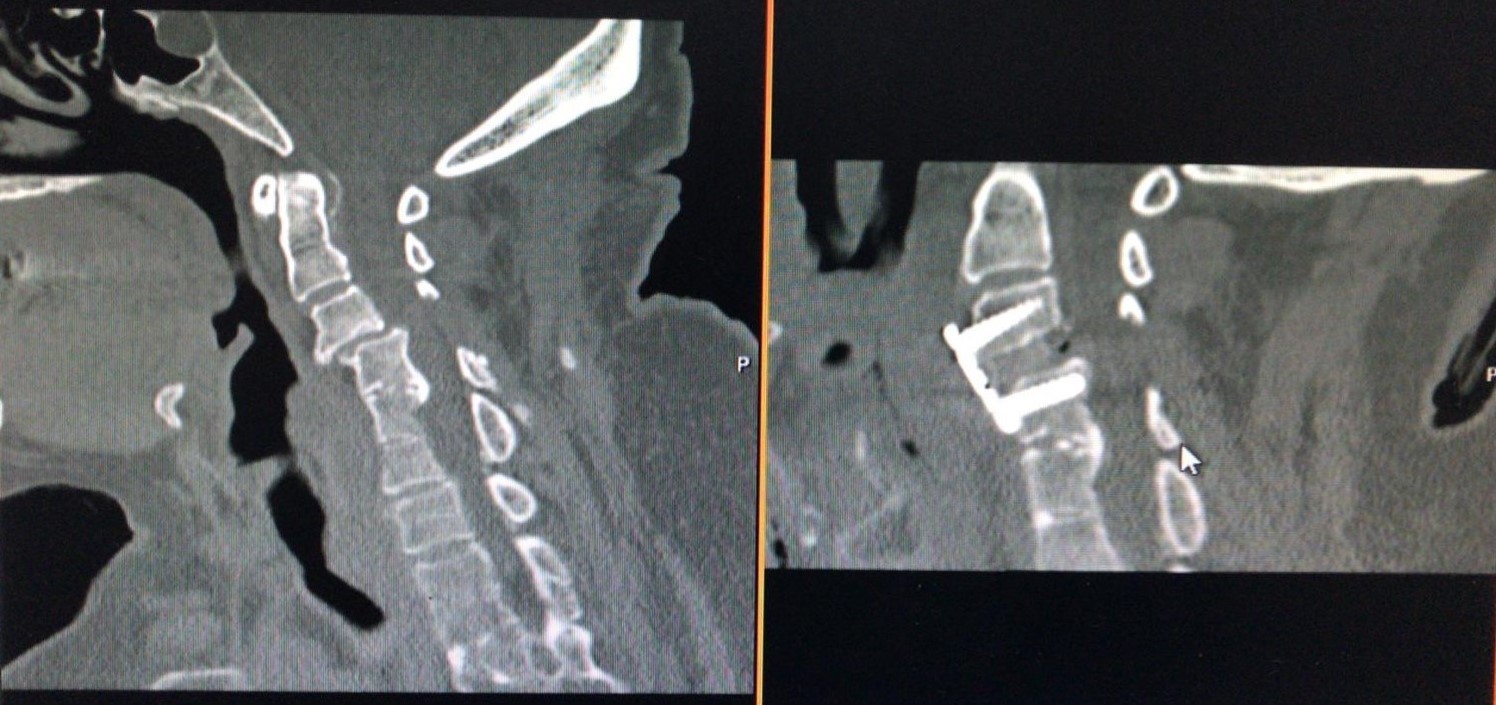

The operative technique was selected concerning our novel “Yilmaz-Yucesoy Classification System” (Table 3). Accordingly, 1 patient (4.54 %) had non-surgical treatment (Yilmaz-Yucesoy Grade 1), 6 patients (27.27 %) received anterior cervical arthroplasty (Yilmaz-Yucesoy Grade 2) (Figure 1), 7 cases (31.81 %) received anterior cervical discectomy or corpectomy and fusion with cervical cage and plate (Yilmaz-Yucesoy Grade 3) (Figure 2). These latter patients did not have cervical spinal instability but had spinal stenosis at more than 1 level. They needed at least 2 level discectomy or corpectomy due to the ossification of posterior longitudinal ligament or osteophyte formation. Eight patients (36.36 %) with cervical spinal instability were performed anterior cervical discectomy or corpectomy and fusion with cervical cage and plate (Yilmaz-Yucesoy Grade 4) (Figure 3).

Figure 3.Computerized tomography scans of a Yilmaz-Yucesoy Classification System Grade 4 patient who underwent anterior cervical discectomy and fusion with cervical cage and plate.